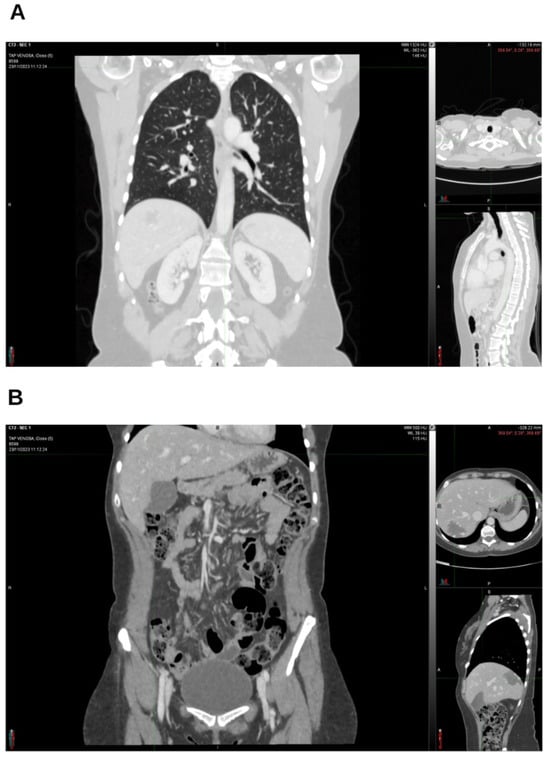

Integrative Use of Cannabidiol, Melatonin, and Oxygen–Ozone Therapy in Triple-Negative Breast Cancer with Lung and Mediastinal Metastases. A Case Report

Background and Clinical Significance: Breast cancer is the most frequent malignancy in women. Metastatic breast cancer is considered a treatable but incurable condition, with a median overall survival of only 2–3 years. Among its subtypes, triple-negative breast cancer (TNBC) accounts for a high proportion of breast cancer-related deaths. It is characterized by an aggressive clinical course, early recurrence, and a strong propensity for visceral and brain metastases. Case Presentation: We report the case of a Caucasian woman who developed systemic disease recurrence with lung and mediastinal lymph node metastases, occurring two years after her primary diagnosis and treatment for TNBC. The patient received three months of chemotherapy combined with an adjuvant integrative protocol consisting of melatonin, cannabidiol, and oxygen–ozone therapy. This combined approach led to the complete disappearance of the lung nodules. Subsequently, stereotactic radiotherapy was performed and, in association with the ongoing integrative treatment, resulted in a significant reduction in mediastinal adenopathy. Introduction of immunotherapy, supported continuously by the same adjuvant strategy, achieved a complete and durable remission. Strikingly, the patient remained disease-free five years after the diagnosis of lung and mediastinal metastases. Conclusions: This clinical case highlights the potential benefit of using melatonin, cannabidiol, and oxygen–ozone therapy as part of an integrative approach in patients with aggressive metastatic TNBC. While it is not possible to establish causality from a single case, the sustained remission observed suggests that such unconventional adjuvant strategies could play a supportive role in enhancing the efficacy of standard oncologic therapies. Full article

Figure 1